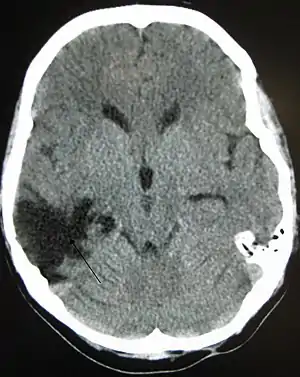

| A CT of the head years after a traumatic brain injury showing an empty space where the damage occurred, marked by the arrow |

There are several imaging techniques that can aid in diagnosing and assessing the extent of brain damage, such as computed tomography (CT) scan, magnetic resonance imaging (MRI), diffusion tensor imaging (DTI) magnetic resonance spectroscopy (MRS), positron emission tomography (PET), and single-photon emission tomography (SPECT). CT scans and MRI are the two techniques widely used and are most effective. CT scans can show brain bleeds, fractures of the skull, fluid build up in the brain that will lead to increased cranial pressure. MRI is able to better to detect smaller injuries, detect damage within the brain, diffuse axonal injury, injuries to the brainstem, posterior fossa, and subtemporal and subfrontal regions. However, patients with pacemakers, metallic implants, or other metal within their bodies are unable to have an MRI done. Typically the other imaging techniques are not used in a clinical setting because of the cost, lack of availability.[37]